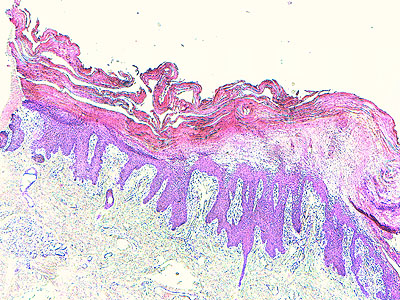

Photo 2 (Hémalun Eosine X 40) : au faible grossissement, l’épiderme revêt un aspect bleu-blanc-rouge,

bleu pour hyperplasie des couches basales, blanc pour vacuolisation des acanthocytes sous-cornés et

rouge pour parakératose de la couche cornée. Le derme est faiblement à modérément inflammatoire.

Légendes de la Photo 2 :

- Flèche bleue : hyperplasie des couches basales

- Flèche blanche : vacuolisation des acanthocytes sous-cornés

- Flèche rouge : pour parakératose de la couche cornée

- Étoile rouge : Le derme est faiblement à modérément inflammatoire